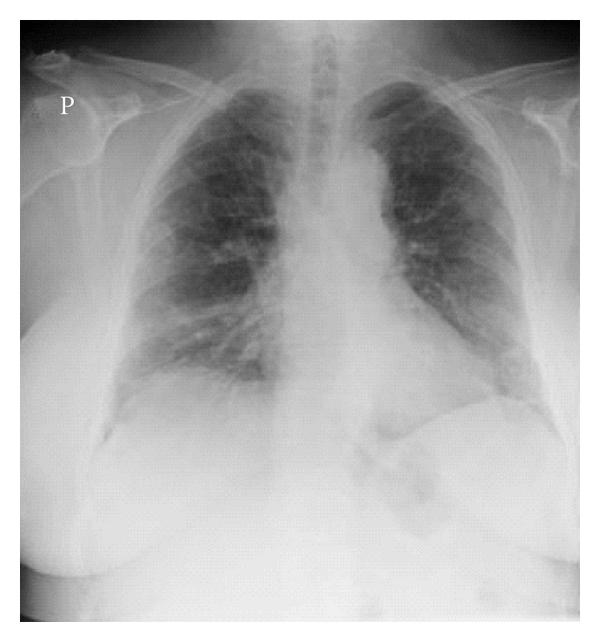

AIP was firstly described by Hamman and Rich in 1935 [22]. For many decades the patients in this first paper were assumed to have been suffering from UIP/IPF, in fact, it was 1990 when these patients were shown to truly suffer from AIP [23]. Clinically AIP presents as a rapid development of respiratory failure in a previously healthy person [24, 25]. Both clinically and radiologically, it usually displays the features of ARDS, but in contrast to ARDS, no specific cause as an aetiology can be found, therefore it could be considered as “idiopathic ARDS” [26, 27] (Figure 1(a)–1(d)). The histological pattern of AIP is typically DAD with hyaline membranes, edema, and interstitial acute inflammation [28]. In the organizing phase of DAD (approximately 5–10 days after injury), alveolar septal thickening with loose organizing fibrosis, type II pneumocyte hyperplasia, and patchy or diffuse airspace organization can be found (Figure 1(c)). The prognosis of AIP is dismal and the mortality high. It has been suggested that by adopting an aggressive diagnostic approach, that is, mechanical ventilation with a lung-protective strategy, and the early institution of immunosuppressive therapy it may be possible to improve the clinical outcome of AIP [29–31]. Controlled prospective studies on the treatment of AIP are not available, not surprising since AIP is so uncommon and it is generally a very acute lung manifestation displaying some overlapping features with ARDS.

(a)

(b)

(c)

(d)